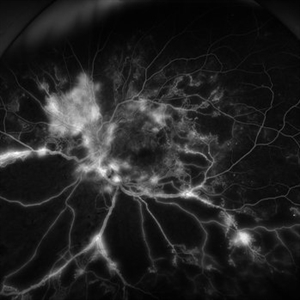

Severe Proliferative Diabetic Retinopathy

Jan 10 2024 by Ahmad B. Tarabishy, MD

33 year old female with 1 month history of vision loss right eye. Severe PDR was noted with VH and a TRD with severe FVP present OD.

Photographer: Sharon Story, Lakeland Eye Clinic

Imaging device: Optos

Condition/keywords: diabetic blindness, fibrovascular proliferation, nonperfusion diabetic retinopathy, peripheral retinal nonperfusion, proliferative diabetic retinopathy (PDR), tractional retinal detachment